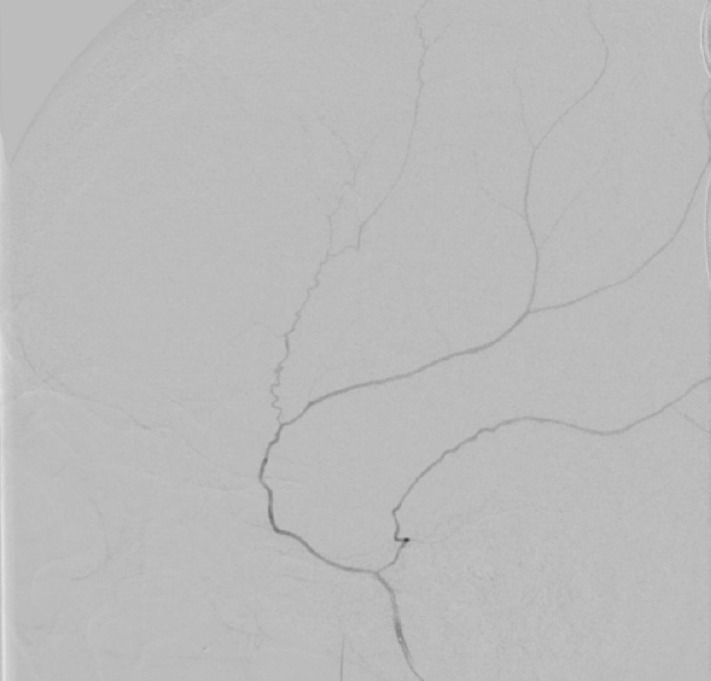

We present a case of a meningo-meningeal arteriovenous fistula (MMAVF) discovered immediately following middle meningeal artery (MMA) microparticle embolization for the treatment of an acute subdural hematoma (SDH). An elderly patient presented with an SDH found during stroke workup. MMA embolization was elected due to his need for therapeutic anticoagulation. During the procedure, multiple MMAVFs appeared after microparticle embolization of the distal MMA branches. We aborted further microparticle embolization and performed coil embolization of the MMA trunk with cessation of flow. No clinical complication was noted postoperatively and no post-procedure hemorrhage was seen. Review of literature suggests that this phenomenon may be associated with microparticle embolization. We hypothesize the cause to be vessel rupture due to barotrauma during manual injection via the microcatheter. As MMA embolization becomes more common, this complication may become more recognized.